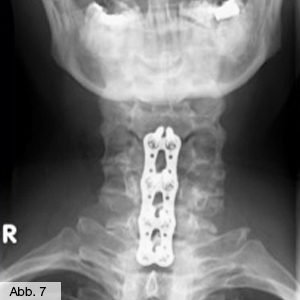

Dieser zusätzliche Knocheneinbau führt oft neben der Stabilisierung auch zu einer Einengung des Spinalkanals oder der Nervenaustrittstellen. Auch bei diesem Krankheitsbild kommen alle oben genannten, nicht-operativen Maßnahmen in unserer Klinik zur Anwendung. Bei fehlendem Erfolg wird dann geprüft, ob ein aufwendiger Eingriff mit Erweiterung des Spinalkanals, Wiederbegradigung und Stabilisierung der Wirbelsäule sinnvoll ist, welcher dann in unserer Klinik durchgeführt wird. Solche Eingriffe führen wir an der Hals-, Brust- und Lendenwirbelsäule durch (Abb. 7 & 8).

Bild Orthopädie Wirbelgleiten